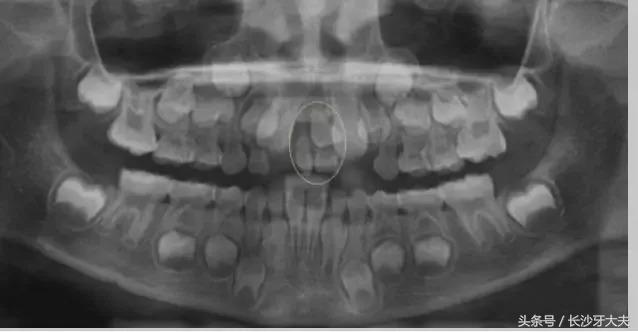

讲了这么多,给大家看一例真实的案例吧:由于多生牙占据了正常门牙应在的位置,两颗门牙还没长出来就被迫分开了很大的距离。

只有去除多生牙的阻碍,以后才可以进行矫正排齐门牙,所以我还是摆脱不了被拔除的命运。

综上所述,多生牙是牙列不齐的重要原因之一,牙医建议,对已萌出和埋于骨内的多生牙,均应尽早拔除;

只有少数身体条件不能耐受多生牙拔除手术的患者,可暂行观察并定期拍片复查。